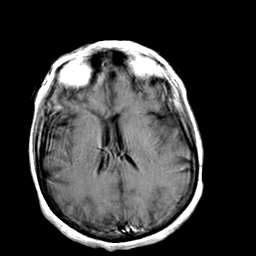

Creutzfeld-Jakob disease: gadolinium enchanced T1-Weighted MR -- Slice #14

[Home][Help][Clinical] Slice 14